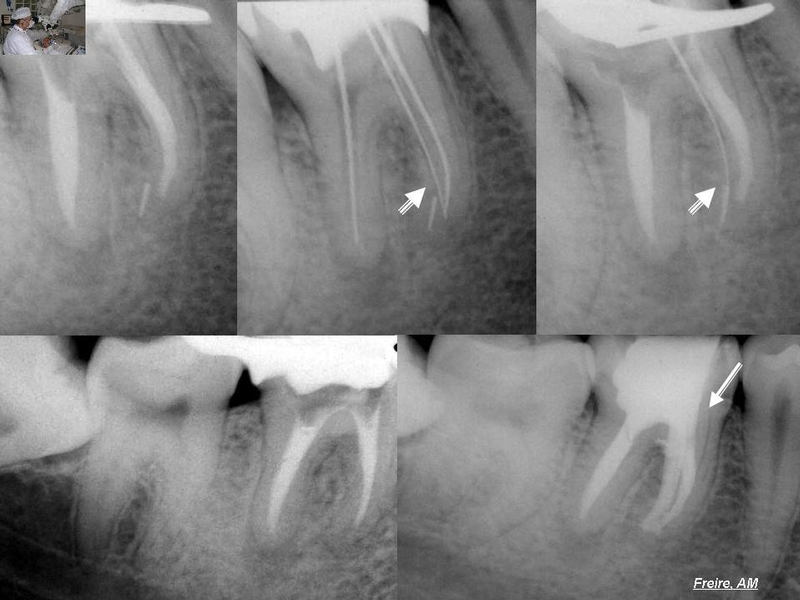

Remoção de instrumentos fraturados

Dentre os acidentes mais corriqueiros temos: fratura de instrumentos no interior dos canais, perfurações corono-radiculares, fratura radicular na tentativa de remoção de um retentor, desvios de canais, sobre-obturações, etc… mas, de longe, a separação do instrumento durante a instrumentação dos canais radiculares tem um percentual maior de ocorrência na clínica diária. Acontecendo, inclusive, entre profissionais mais experientes.

Existem situações que causam grandes dúvidas até em  profissionais mais experientes. Casos em que a prótese encontra-se bem adaptada e realizada há pouco tempo… instrumentos fraturados em locais de difícil acesso, quanto mais calibroso o instrumento fraturado, mais difícil de remover… pelo simples fato de que nestes casos o instrumento fraturou por torção e não por fadiga, e encontra-se preso em uma das paredes.  Geralmente a fratura por fadiga deixa o instrumento mais acessível à remoção. Portanto em casos de dúvidas a responsabilidade é maior, e o profissional deverá estar preparado e bem equipado. Está seguro do procedimento?… então, mãos a obra!!!